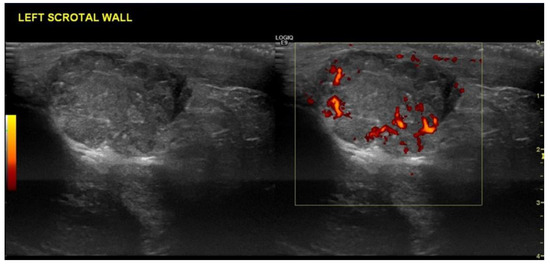

4.1. Seminomatous Germ Cell Tumour

| Seminomas | Homogenous and hypoechoic Well circumscribed Occasionally contain cystic components or calcifications |